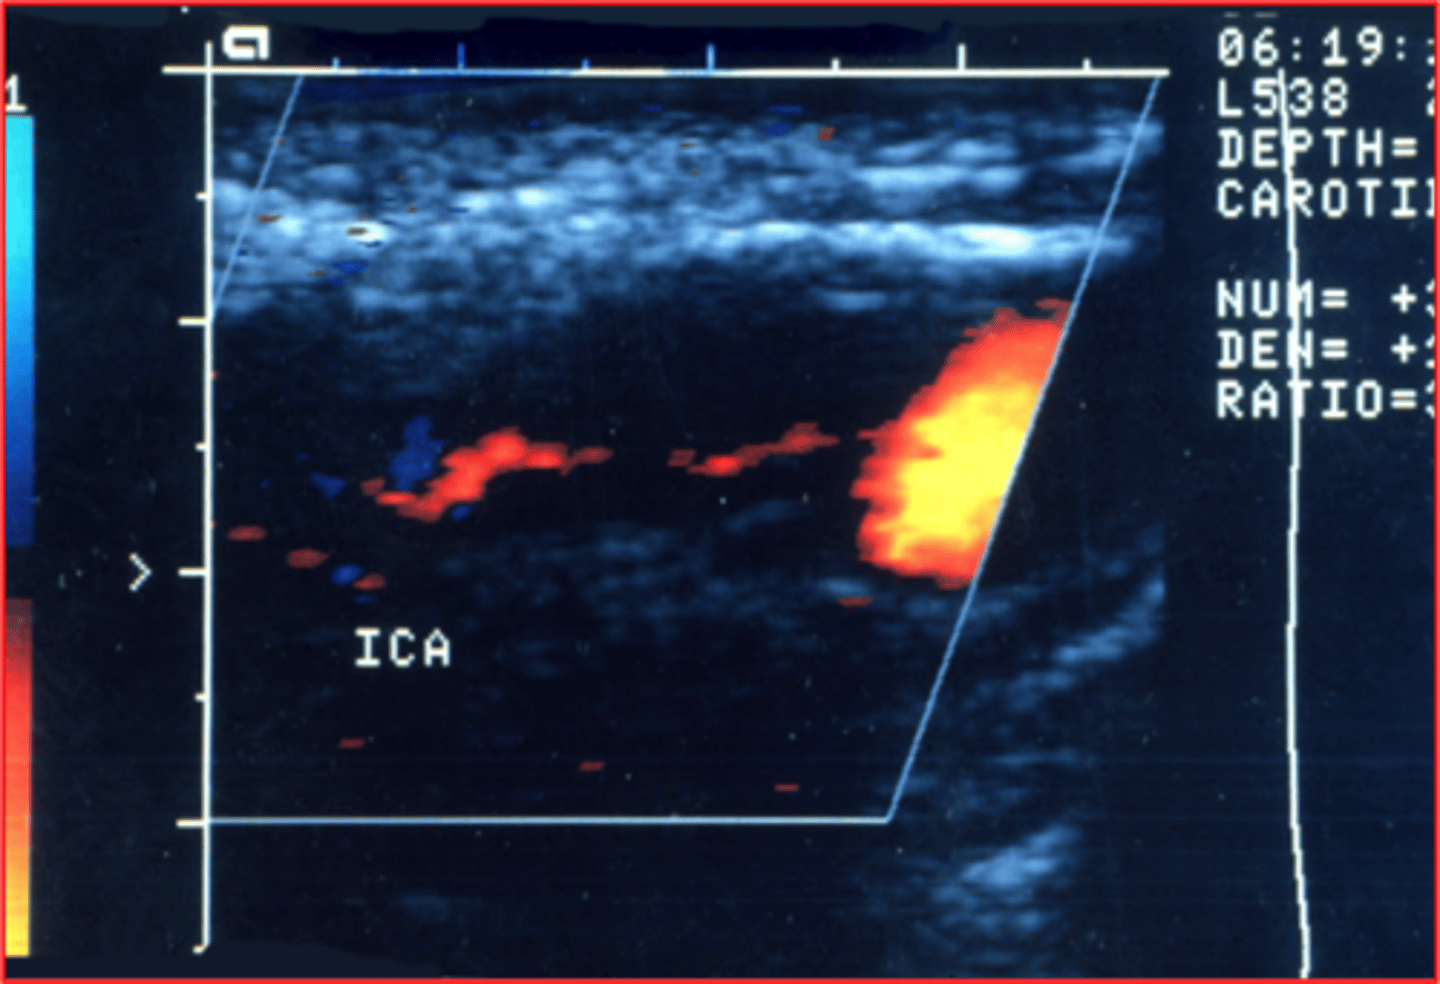

External carotid artery

Which normal cerebrovascular vessel demonstrates the highest flow resistance?